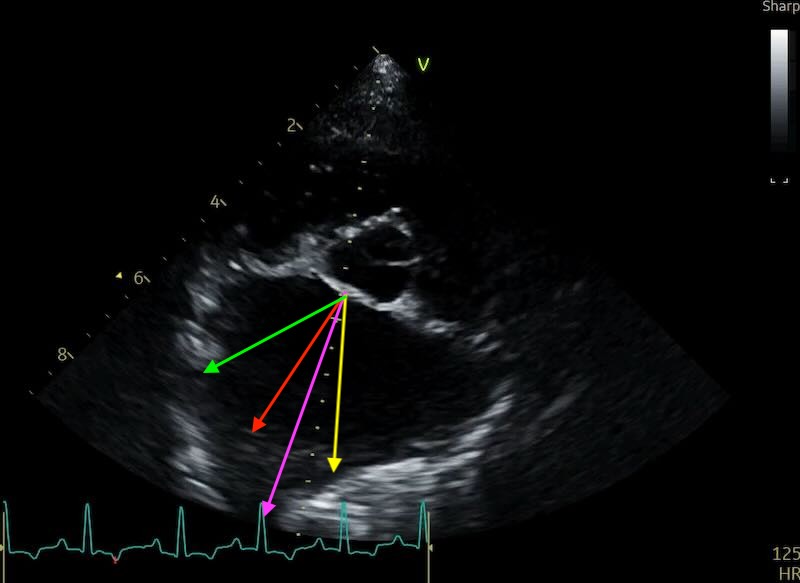

One of the most frequent challenges in the short-axis view is the “disappearing” posterior wall of the left atrium. The pulmonary veins enter the atrium at its caudolateral aspect, and because the wall here is incredibly thin, it often suffers from ultrasound dropout.

When this happens, the blood in the atrium and the blood in the vein appear to merge into one large anechoic space. If you simply place your caliper at the first visible tissue interface, you will inadvertently include the pulmonary vein in your measurement, leading to an artificially high LA:Ao and a potential misdiagnosis of Stage B2 MMVD.

Here are 2 examples of a normal LA with a pulmonary vein, and a very enlarged LA also having pulmonary vein issues:

The Clinical Workaround: If you see a vein entering the atrium, do not measure into the vessel. There are multiple described approaches for coping with this, and as yet no consensus on the best approach:

- Option 1: “approximate” the atrial border by connecting the visible edges of the atrium with an imaginary curved line that follows the natural contour of the chamber. If the dropout is so severe that you are guessing, it is time to move to a different view.

- Option 2: Angle your measure to the little ‘bump’ that sits just to the right of the vein.

- Option 3: Angle your measure to the wall where it first becomes visible to the left of the vein

Personally, I’m a fan of option 2. But set guidelines if published will maybe solve this debate for good…